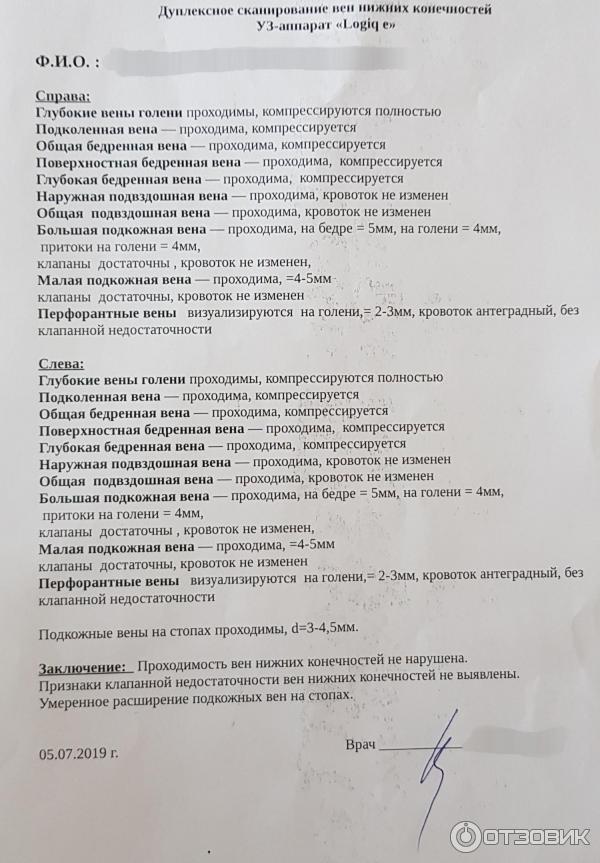

ЦДК сосудов почек: что это и как проводится